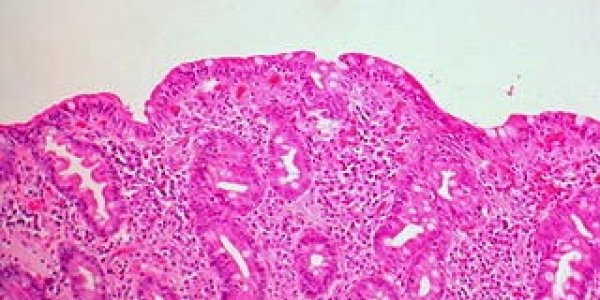

Like everything else in science and medicine, there is modern controversy about circumcision. In the United States the rate of circumcision is around 81%. A paper in Mayo Clinic Proceedings finds…